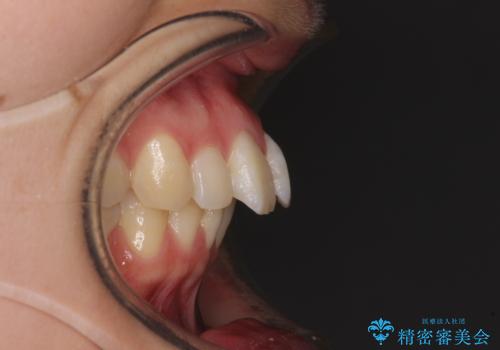

左右ともに奥歯の咬み合わせが上顎前突となっており、上顎前歯が飛び出している状態でした。

奥歯の咬み合わせ改善が必要であるため、マウスピース矯正より確実に達成のできるワイヤー矯正にて治療を行うこととしました。